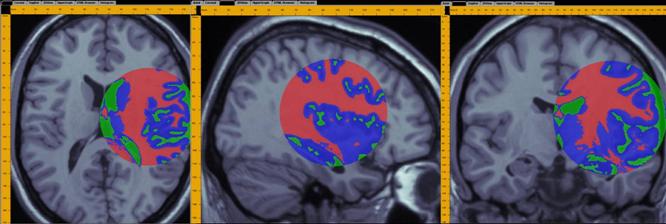

A demonstration of a 3D data analysis using the SOCR EM Mixture model is included in the LONI Viz Manual (http://www.loni.ucla.edu/download/LOVE/LOVE_User_Guide.pdf). This example shows how 3D brain imaging data may be segmented into three tissue types (White Matter, Gray Matter and Cerebra-spinal Fluid). This is achieved by LONI Viz (Dinov et al., 2006) sending the segmentation tasks to SOCR and SOCR returning back the 3D segmented volumes, which are superimposed dynamically on top of the initial anatomical brain imaging data in real time. The figure below illustrates this functionality. Other external computational tools could also invoke SOCR statistical computing resources directly by using the SOCR JAR binaries (http://www.socr.ucla.edu/htmls/SOCR_Download.html) and the SOCR Documentation (http://www.socr.ucla.edu/docs).